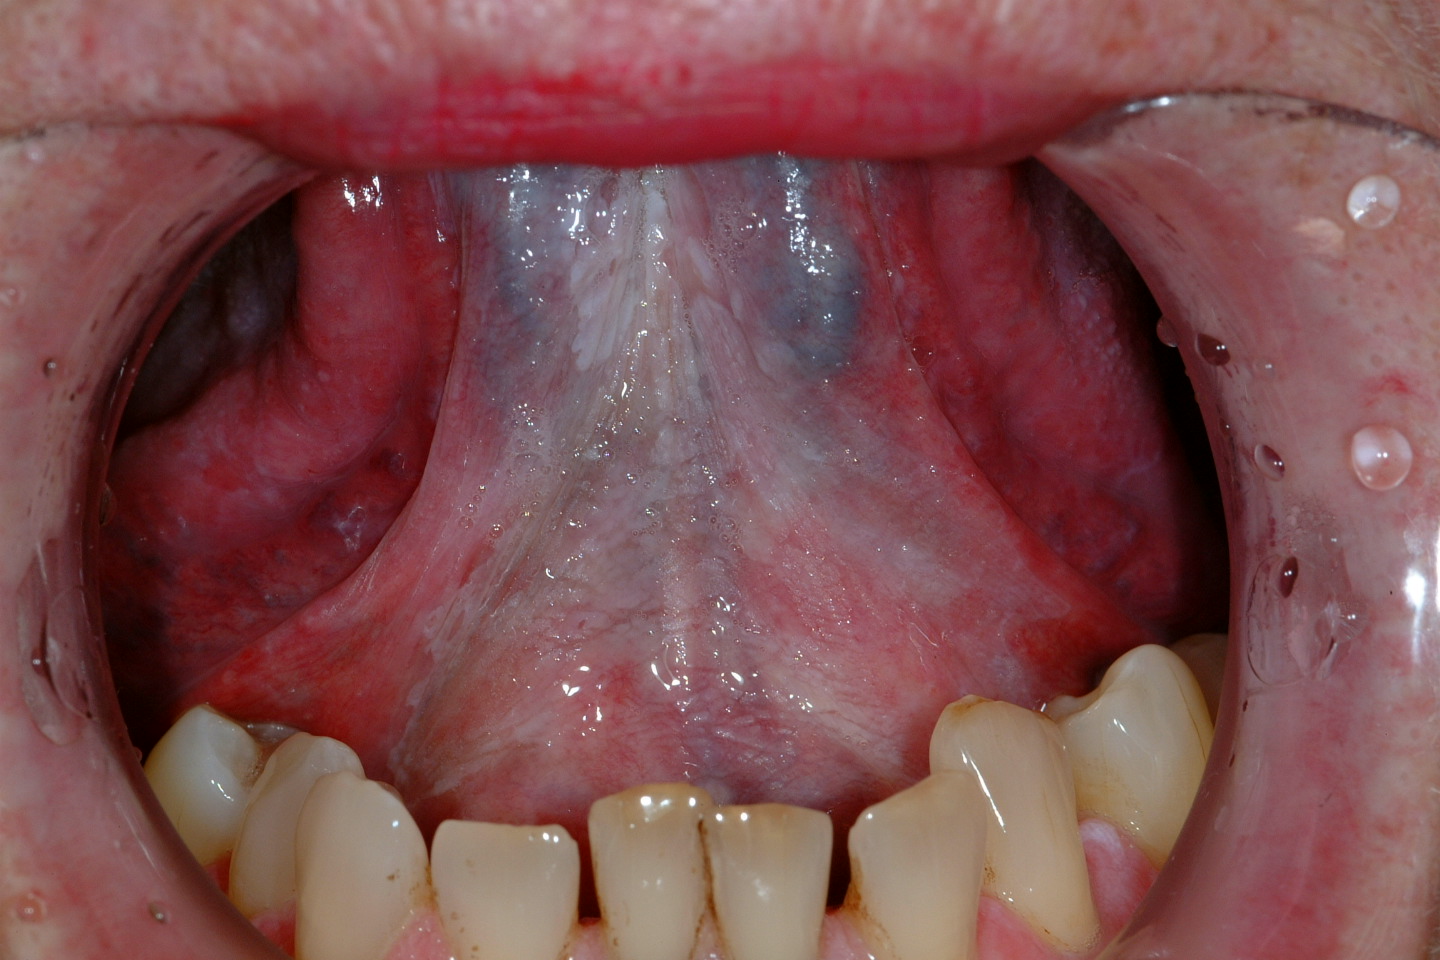

An oral leukoplakia (WHO definition) is a white patch or plaque that cannot be characterized, clinically or histopathologically, as any other disease. Erythroplakia can be similarly described but for bright red patches or plaques. Erythroleukoplakia (speckled leukoplakia) forms the third lesion commonly associated with risk of malignant transformation. This risk has been reported to be 2-6% for leukoplakia (varies with sites, e.g. highest in floor of mouth). 40-50% of erythroplakias have high grade dysplasia or carcinoma present. Speckled leukoplakia is of intermediate risk.

Figure 1: An example of leukoplakia, anterior floor of the mouth.

Other lesions associated with malignant transformation include chronic hyperplastic candidiasis, submucous fibrosis and sideropenic dysphagia. Less commonly, certain conditions such as dyskeratosis congenita (tongue leukoplakia); discoid lupus erythematosus (lip cancer) and lichen planus (1-3% incidence, lichenoid dysplasia main reason) have a risk of malignant change.